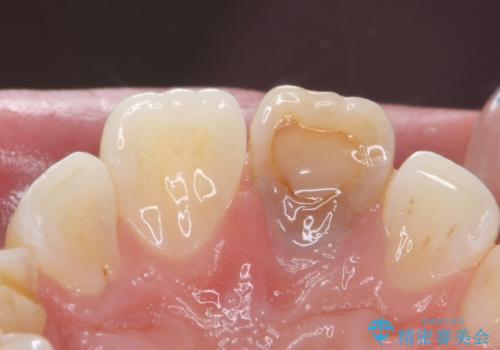

変色した前歯 ジルコニアクラウンでの修復

- 前歯の変色を主訴に来院された患者様です。

根管治療からのやり直しをした後、ジルコニアクラウンで色調の改善をしていきます。

歯の黒ずみを完全に見えなくすることができ、大変喜んでいただけました。

被せ物を装着する際は、歯の中(根管)から綺麗にすることも重要となります。